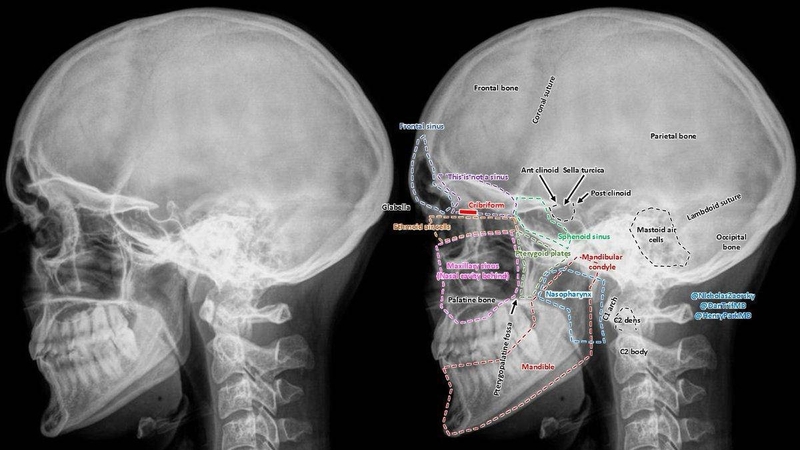

Trước khi tiến hành phẫu thuật hạ gò má, bệnh nhân sẽ được bác sĩ thăm khám kỹ lưỡng để đánh giá tình trạng khuôn mặt và sức khỏe tổng quát. Sau đó, các bước chụp phim khuôn mặt từ nhiều góc độ, CT hàm mặt và X-quang xương sọ - hàm mặt sẽ được thực hiện nhằm cung cấp hình ảnh chi tiết về cấu trúc xương.